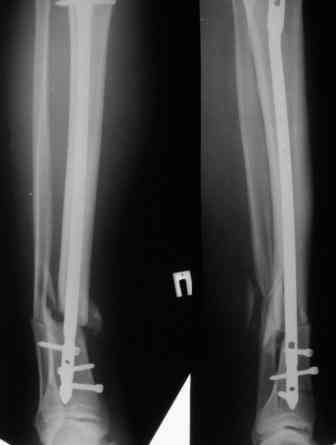

У молодого человека, у которого еще есть перелом тела поясничного позвонка, выполнен синтез голени.

Ротационная подвижность пока устраняется дополнительной гипсовой лонгетой.Из двух вопросов "кто виноват" и "что делать" предлагаю ответить на второй. Мое предложение:удалить гвоздь, наложить аппарат, добиться репозиции,забить этот же гвоздь, на этот раз с блокированием через отверстия гвоздя.Кроме моего высказаны следующие предолжения:1) заблокировать как есть нижние отверстия;2) наложить снаружи аппарат для стабилизации, в таком виде ждать сращения;3) перейти на лечение аппартом;4) перейти на лечение гипсовой лонгетой, так как все-равно перолом позвоночника-месяц лежать. Ваше мнение? Спасибо. Снимки в архиве.

Здравствуйте коллега! Интересный случай! Буквально 3-4 месяца назад столкнулся с подобной ситуацией. Плюс у больного имелась нейропатия малоберцового нерва, стойкая эквинусная деформация стопы. Молодой человек лечился в другом лечебном учреждении. Первым этапом выполнено удаление стержня ChM, наложен аппарат внешней фиксации, в течении недели проводилось устранение имеющихся деформаций. Вторым этапом выполнен ЗИМО стержнем MetaDiaFix-T большего диаметра (картинки в приложении).